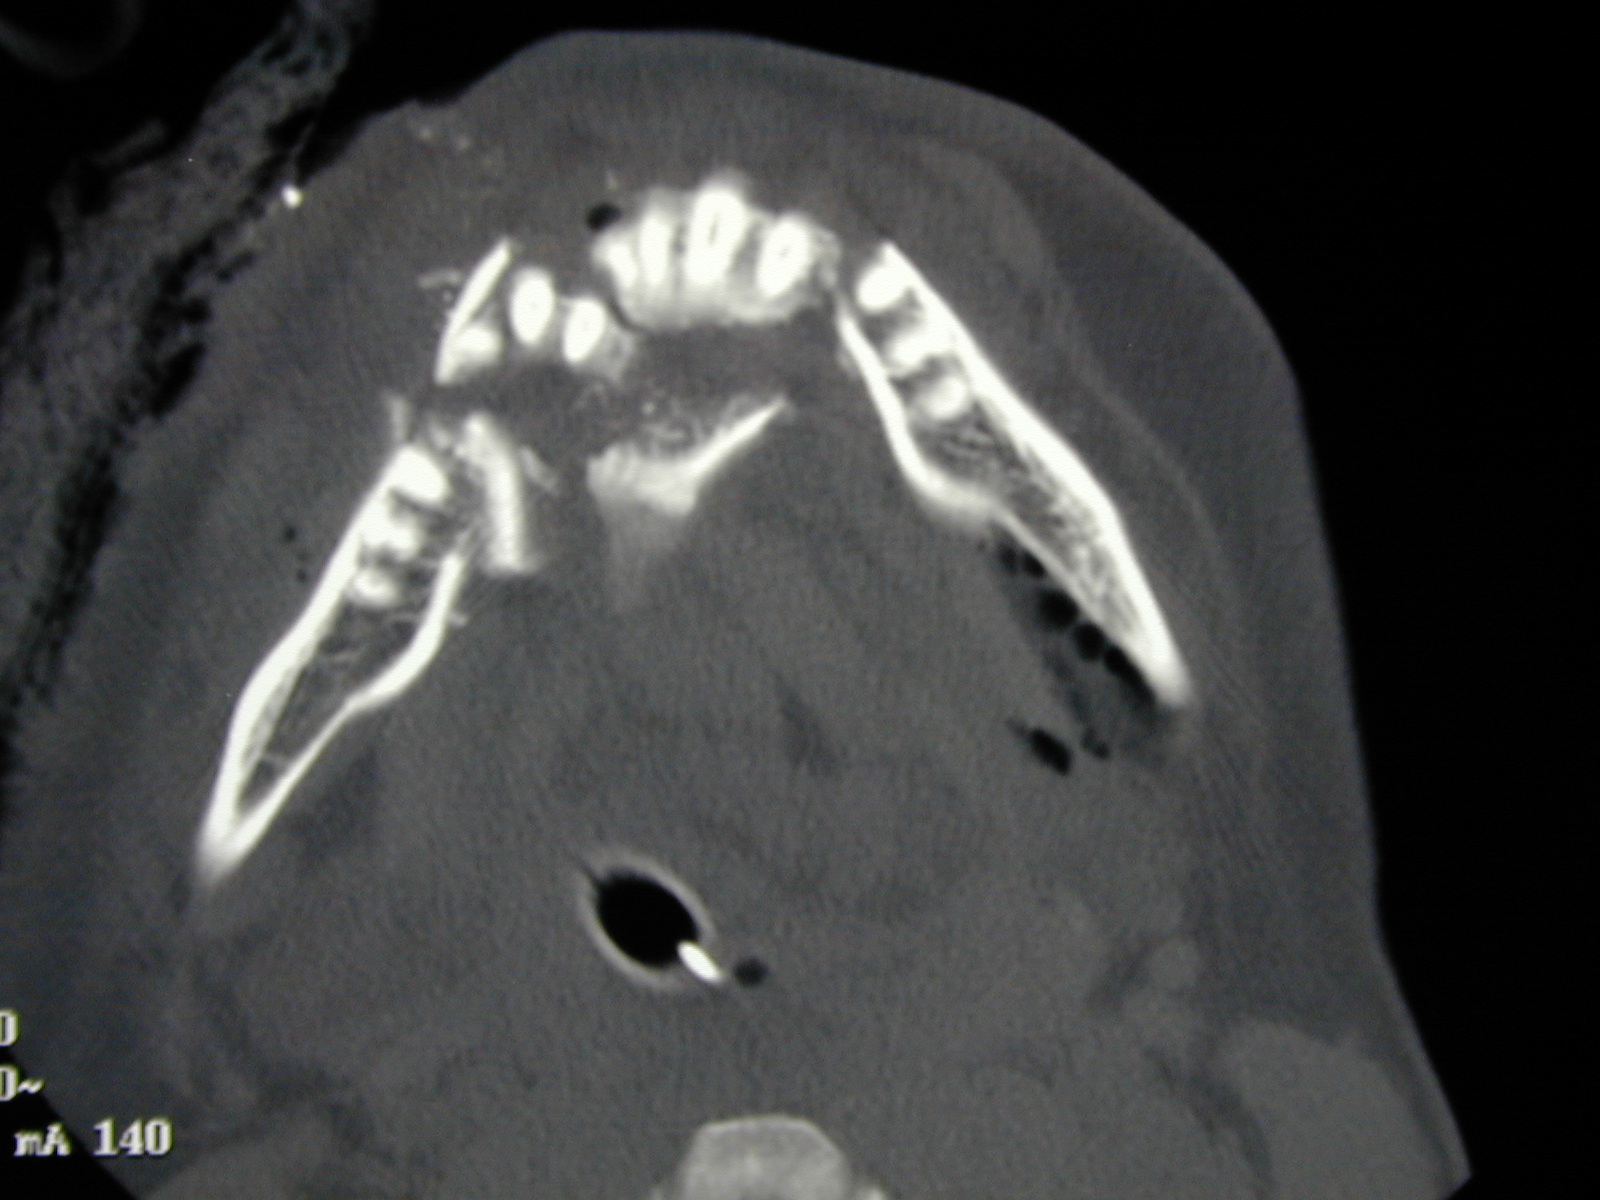

Figure 10: CT scan of a comminuted fracture (crushed and splintered bone) of the mandible, caused by a gunshot wound